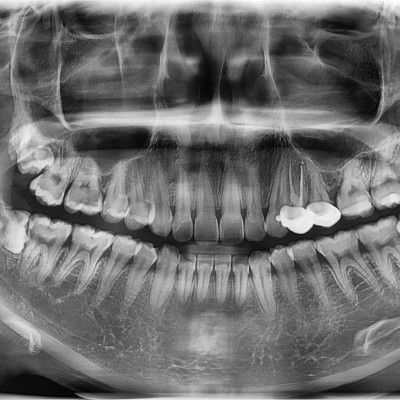

#18,28,38 48 사랑니 발치 #18,28,38,48 사랑니 발치 구강 외과 전문의가 당일 발치했습니다. ----------------------..

작성자 이턱이 작성일 02-04 조회 1